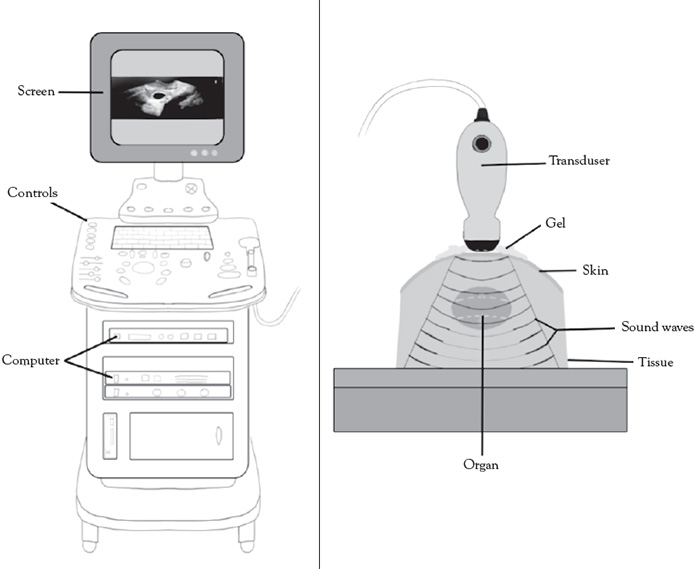

Ultrasound is a type of mechanical (not electrical) energy collectively known as sound energy. The normal human range of sound is between16 Hz 20,000 Hz (1 MHz = 1 million cycles per second), with higher end of the spectrum seen in children and young adults. Ultrasonic frequencies beyond 20,000 Hz and can be applied in both therapeutic and diagnostic applications. The frequencies generally used in therapy are typically between 1–3 MHz for deeper tissues and 2–20 MHz in diagnostic ultrasound studies. Ultrasound beams are emitted by handheld devices, called transducers, which are mechanized high-frequency sound generators [13,14]. Figure 1 illustrates a schematic of a basic ultrasound system.

All body tissues will impede the passage of ultrasound waves, with variability based on tissue density and elasticity. The presence of air and metal will effectively impede nearly 100% of the beam resulting in no effective transmission. For this reason, a coupling gel (typically water-based) is used to maximize contact between the imaging transducer and body tissues for optimal ultrasound wave transmission [19].